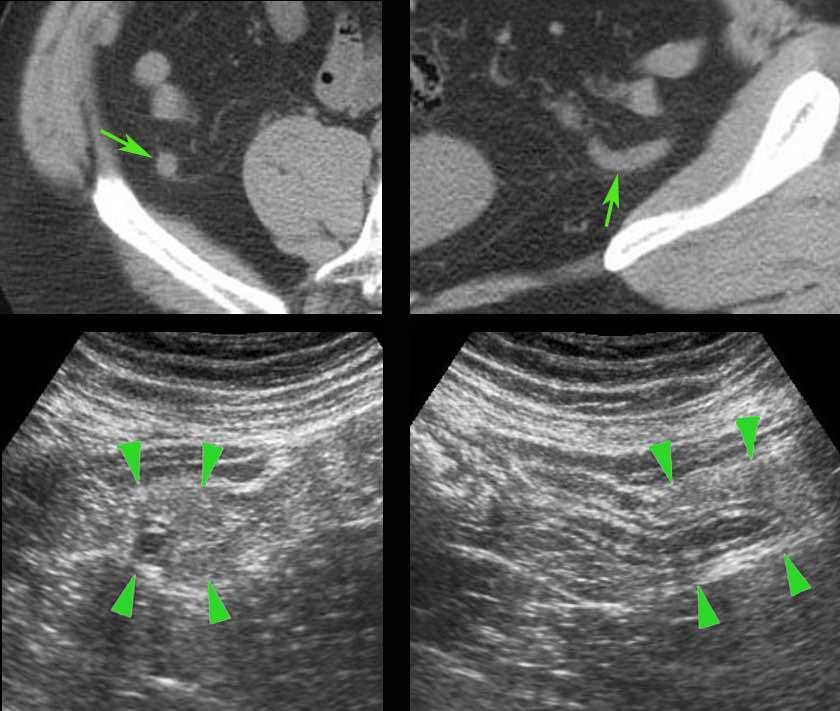

Điều thú vị là trong giai đoạn sớm của viêm mô mỡ, siêu âm nhạy hơn CT.

Ở bệnh nhân này với đau hố chậu phải kéo dài 18 giờ, CT chỉ cho thấy hình ảnh thâm nhiễm mỡ tối thiểu xung quanh ruột thừa 8,5 mm (mũi tên).

Siêu âm với kỹ thuật ép có kiểm soát đã cho thấy rõ ràng mô mỡ viêm tăng âm, không thể ép xẹp (đầu mũi tên) xung quanh ruột thừa.